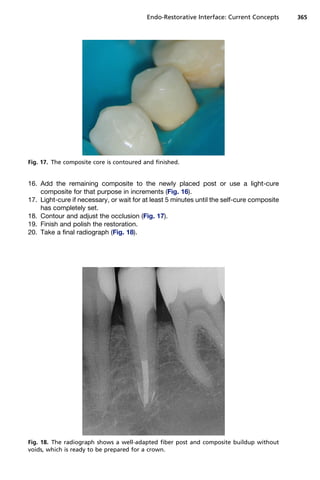

Fig. 17. The composite core is contoured and finished.

16. Add the remaining composite to the newly placed post or use a light-cure

17. Light-cure if necessary, or wait for at least 5 minutes until the self-cure composite

has completely set.

18. Contour and adjust the occlusion (Fig. 17).

19. Finish and polish the restoration.

20. Take a final radiograph (Fig. 18).

Fig. 18. The radiograph shows a well-adapted fiber post and composite buildup without

voids, which is ready to be prepared for a crown.